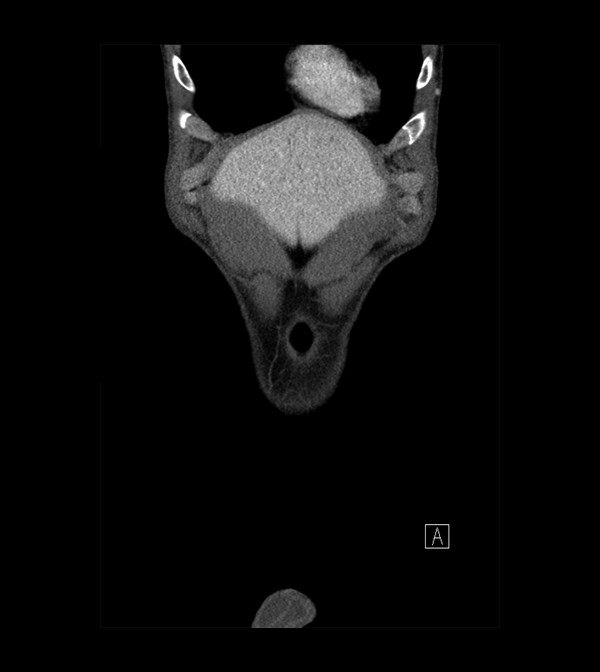

Body

Covers abdominal CT anatomy.

Pelvis

Covers pelvic MRI anatomy.